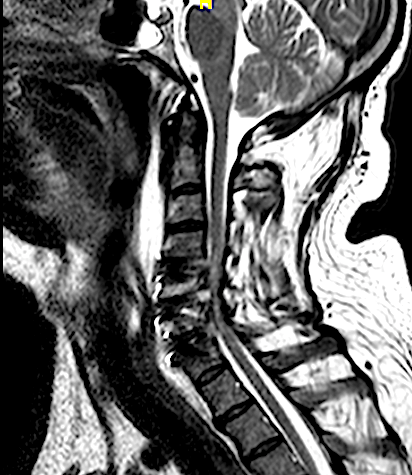

El resultado de la RM cervical planteaba dudas si era necesario o mandatorio realizar una descompresión posterior complementaria. Sin embargo, los parámetros clínicos no sugerían una compresión medular: la evolución lenta a la mejoría de su paresia, la ausencia de progresión de su mielopatía y la ausencia de dolor resultaron determinantes para que se adoptara una actitud conservadora. El paciente fue dado de alta (en plena pandemia de covid) y la evolución fue buena a pesar de que no pudo completar la rehabilitación. Se realizó nueva RM y RX cervical a los seis meses que resultó mucho más concluyente.

A los seis meses de evolución, el paciente sigue pendiente de rehabilitación, ha mejorado su inestabilidad postural y en la marcha aunque persiste la paresia C7 (agravada respecto a preoperatorio, con EMG y registros MNIO con radiculopatía crónica severa).

RM 6 meses

afecta de manera significativa el diámetro del canal vertebral y a la que se realizará seguimiento evolutivo.